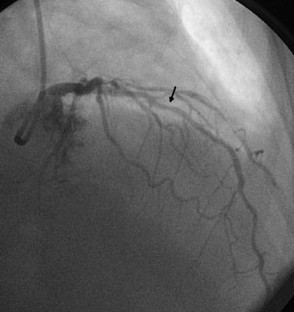

Fractional flow reserve (FFR) is a standardized and well-established method frequently used in clinical practice to evaluate the hemodynamic significance of epicardial coronary stenosis identified by coronary angiography. It is based on the change in the pressure gradient across the stenosis after the achievement of maximal hyperemia of the coronary circulation which is commonly induced by intravenous (IV) or intracoronary (IC) administration of adenosine. Here, we have described three cases of IC adenosine-induced ventricular arrhythmias during FFR measurement from our institution, and after literature review we found that all the cases of ventricular arrhythmias induced by adenosine during FFR measurement were observed where it was administered via IC route. Although a causal relationship between the use of IC adenosine during FFR measurement and the induction of ventricular arrhythmias is not yet established, we suggest using IV adenosine as the preferred route of administration until we better understand the incidence and mechanism underlying this phenomenon.

Raffaele P, Tullio N, Giuseppe G, et al. Adenosine-induced torsade de pointes complicating a fractional flow reserve measurement in a right coronary artery intermediate stenosis. Cardiovasc Revascularization Med. 2013;14:118–20.

Shah AH, Chan W, Seidelin PH. Ventricular fibrillation precipitated by intracoronary adenosine during fractional flow reserve assessment: a cautionary tale. Heart Lung Circ. 2015;11:e173–5.